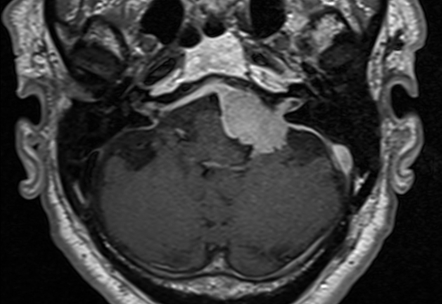

Meningiomas of the CPA

Epidermoid tumor of the CPA

Benign tumor composed of squamous epithelial elements.

Thought to arise from congenital nests.

Glomus tumor of the CPA